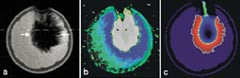

Det som karakteriserer dagens bildeopptak er først og fremst kortere opptakstid enn tidligere. Endringen har for enkelte applikasjoner vært dramatisk. Et T2-vektet bildeopptak av leveren kunne i slutten av 1980-årene ta bortimot 20 minutter. I dag kan opptaket gjøres mens pasienten holder pusten, dvs. i løpet av 15 – 20 sekunder, og det med en betydelig bedret bildekvalitet (fig 2). Prinsippene for de opptaksteknikkene (i MR kalt pulssekvenser) som i dag benyttes til raske opptak, er ikke av ny dato, men bedrede gradienter og spoler har gjort at disse teknikkene nå også kan gi god bildekvalitet. Den aller raskeste teknikken kalles ”echo planar imaging” (EPI) og kan i sin hurtigste versjon klare opptakstider ned mot 20 ms. EPI-teknikker blir mye benyttet til avbildning av perfusjon, diffusjon og blodets oksygeneringsgrad.

Moderne datateknologi med programvare for avansert bildebehandling har gjort det mulig å ekstrahere og presentere ny informasjon fra bildedataene. Metoder som ”volume rendering” og segmentering gjør det mulig å avgrense, fargekode og volumbestemme normale og patologiske anatomiske strukturer (fig 3). En lang rekke parametriske bilder kan kalkuleres, dvs. bilder der kontrasten eller fargekodingen gjenspeiler ulike parametere som f.eks. grad av hjerneaktivitet, diffusjonskoeffisienten i et vev eller hastigheten av et kontrastmiddelopptak eller kontrastmiddelpassasje i ulike vev.